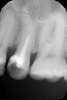

Marina_A Опубликовано 6 июня, 2013 Поделиться Опубликовано 6 июня, 2013 Пациентка пришла с целью санации).Я посмотрела на снимок очередного зуба и ахнула Но все оказалось не так плохо, нам удалось пройти каналы. ну и конечно же, как без паффа? зато какой четкий знак вопроса! 8 Ссылка на комментарий

Kivilgar Опубликовано 6 июня, 2013 Поделиться Опубликовано 6 июня, 2013 Пациентка пришла с целью санации).Я посмотрела на снимок очередного зуба и ахнула 1.PNG Но все оказалось не так плохо, нам удалось пройти каналы.2.PNG ну и конечно же, как без паффа? зато какой четкий знак вопроса! 3.PNGЗдорово получилось. Какими файлами? Ссылка на комментарий